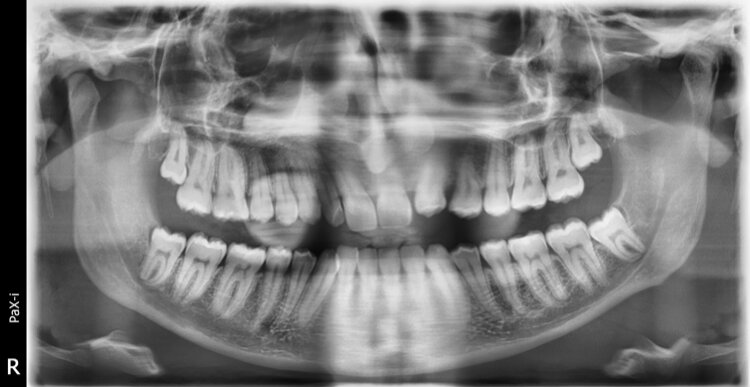

They want me to get elastic braces and see what we do maybe move with invisalign or whatever is best needed for my treatment. If you have decent knowledge in this field respond and give advice for treatment. pls don’t message if u don’t know anything low iq type move

If they are moving my jaw back I would know and not continue with him he wanted to do extractions but I told him I wanted to avoid recession so we are doing regular braces.